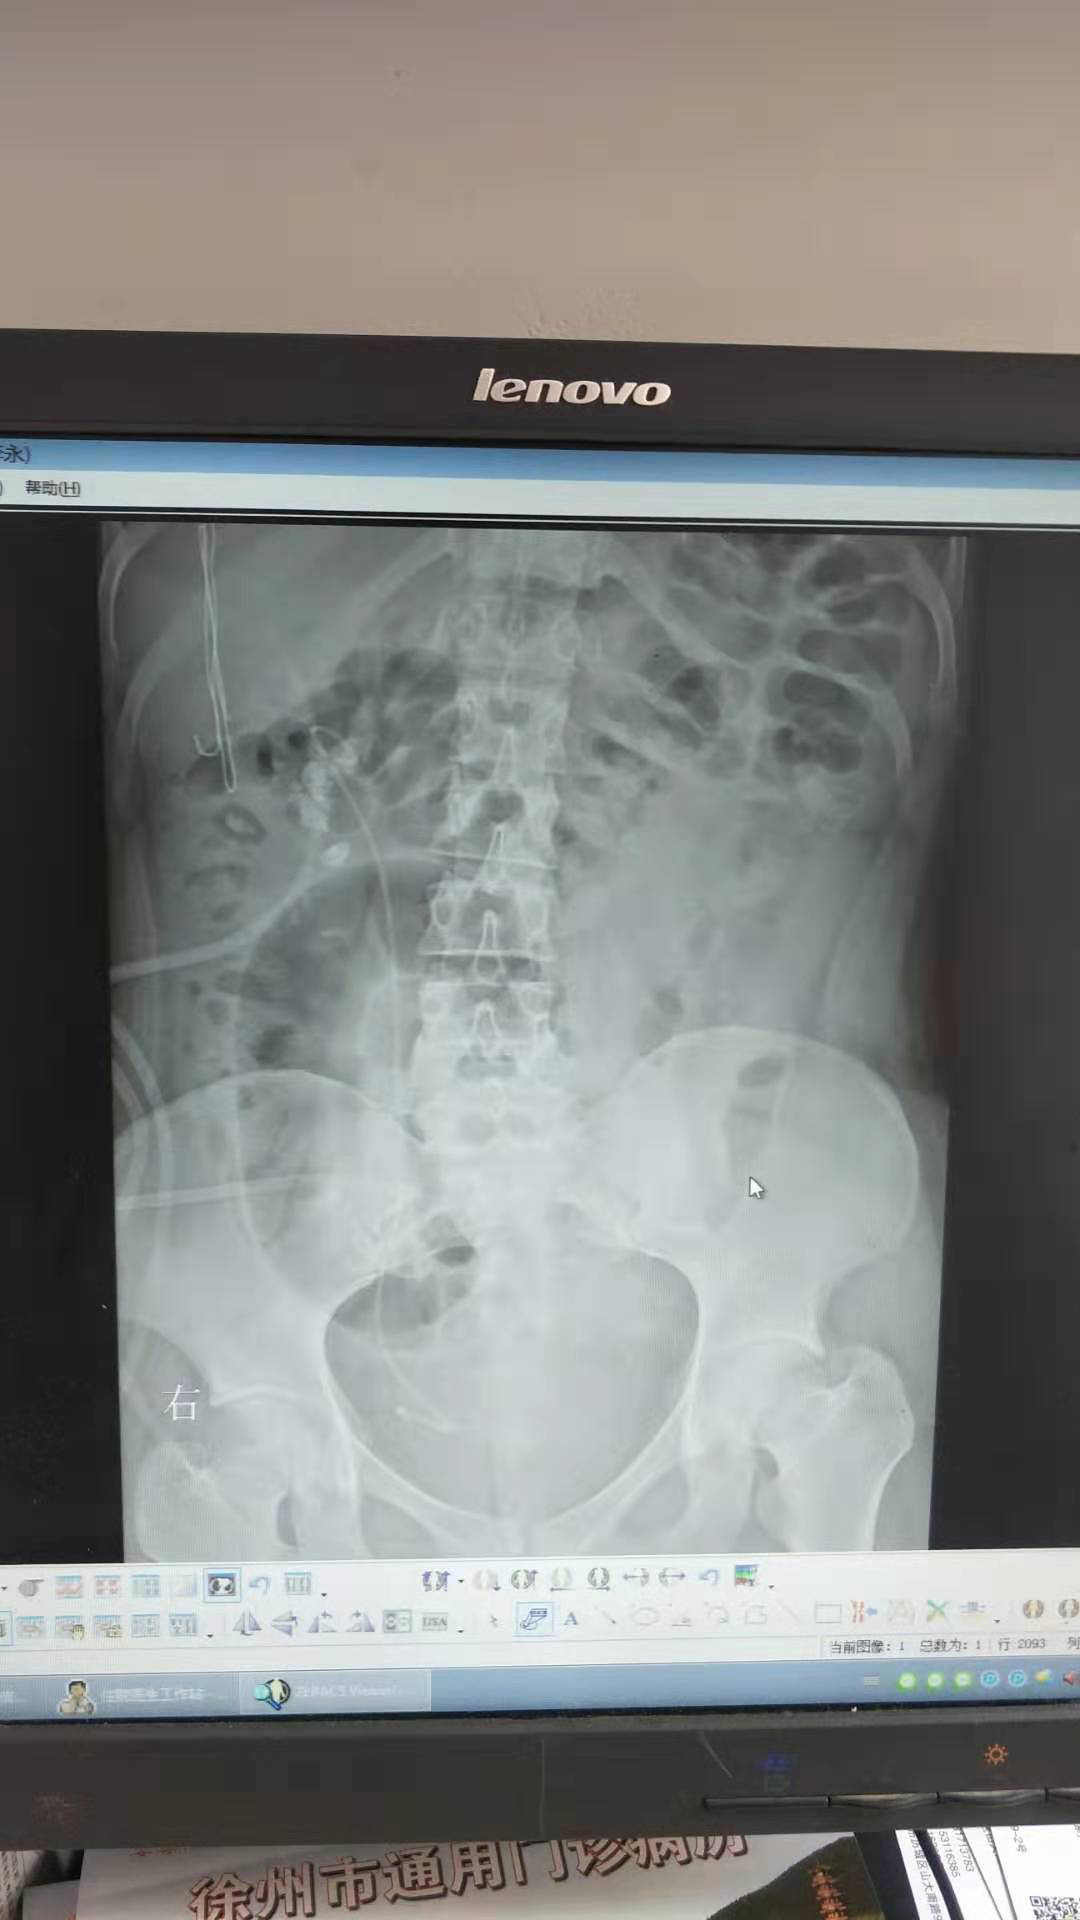

患者:王嬌,女性,21歲。因“體檢發(fā)現(xiàn)右腎結(jié)石8月余”入院,診斷為右腎多發(fā)結(jié)石、右輸尿管結(jié)石、右腎積水。于2019-07-17在全麻下行“輸尿管軟鏡聯(lián)合經(jīng)皮腎鏡右腎結(jié)石碎石取石術(shù)”, 此術(shù)式采取側(cè)仰臥奔跑位,為我科首次采用輸尿管軟鏡聯(lián)合經(jīng)皮腎鏡處理復(fù)雜性腎結(jié)石。優(yōu)點為軟性輸尿管鏡可以觀察和處理經(jīng)皮腎鏡不能達到的腎盂、腎盞內(nèi)的結(jié)石,配合鈥激光碎石效果滿意。對于腎臟復(fù)雜性結(jié)石清除率較高,效果良好,術(shù)后恢復(fù)快,5天后康復(fù)出院,對治療表示滿意。